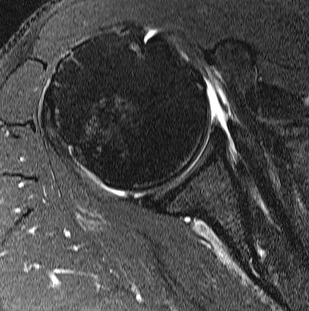

Full thickness retracted subscapularis tear with medial dislocation of long head of biceps tendon